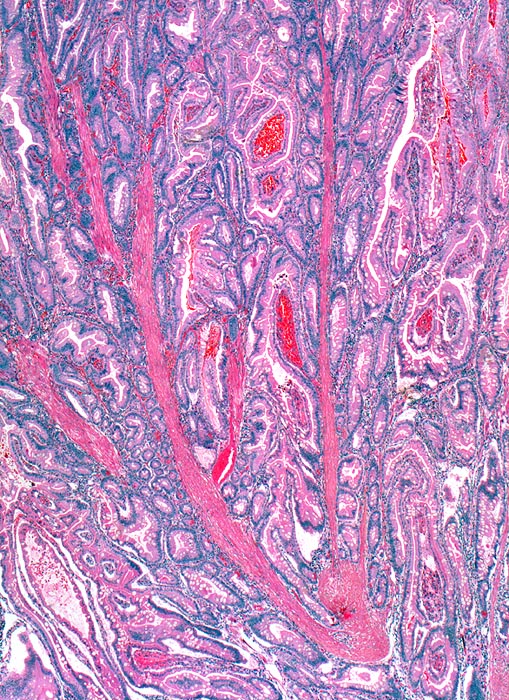

AP/ Peutz-Jeghers Polyp, Dünndarm

Peutz-Jeghers Polyp, Dünndarm

Jejunum